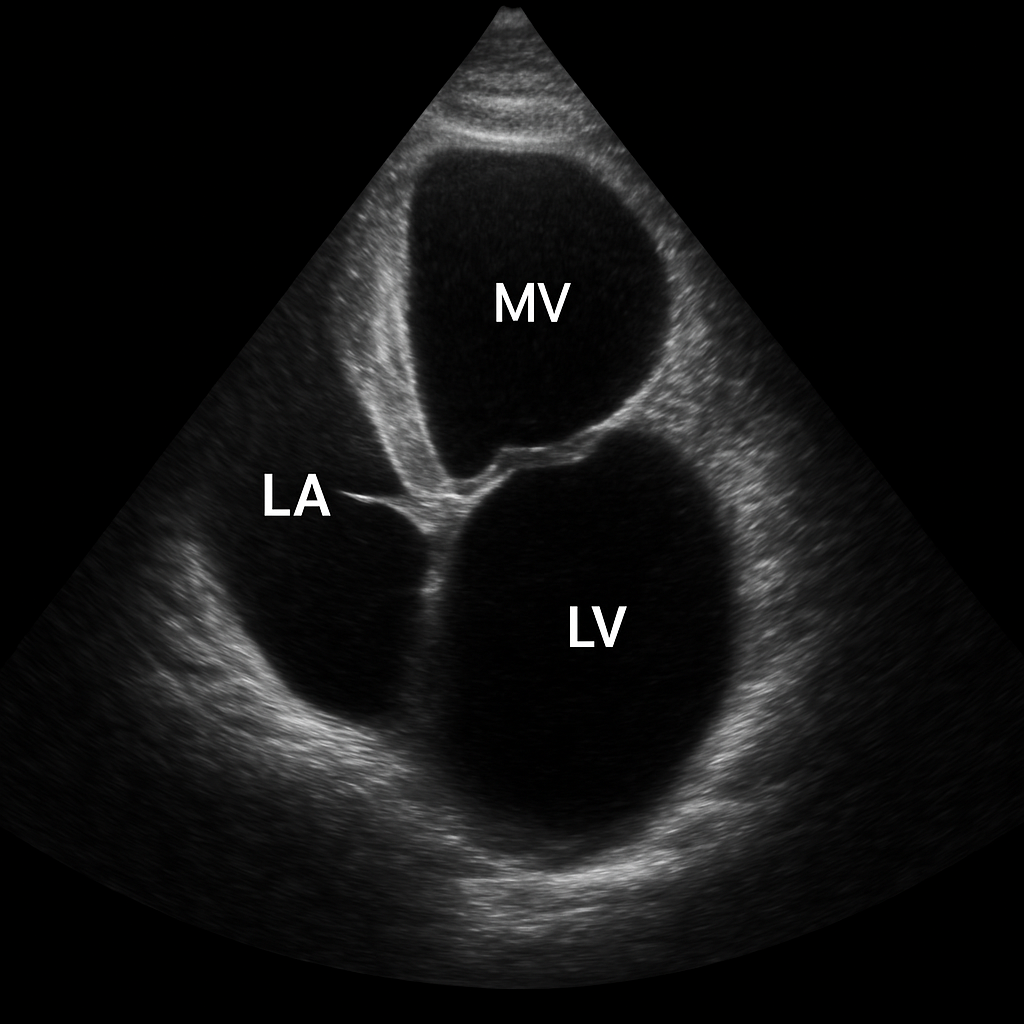

Echo — Apical Two-Chamber

Transthoracic echocardiogram apical two-chamber (A2C) view showing the left atrium, mitral valve, and left ventricle with anterior and inferior walls.

ULTRASOUND AI Generated 2026-03-16

Apical Two Chamber

2D B-mode TTE, apical 2-chamber. Show LA, MV, LV anterior and inferior walls.